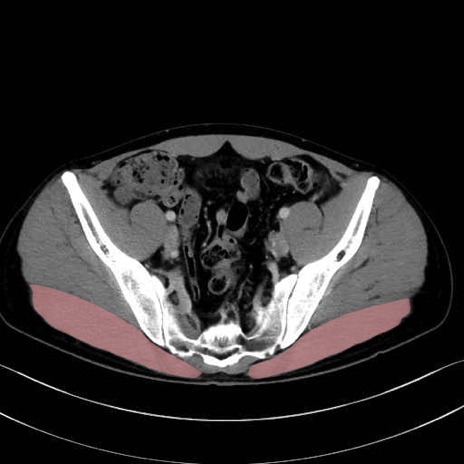

3. 殿部の筋肉(表層・中層・深層)

大殿筋 (Gluteus maximus)